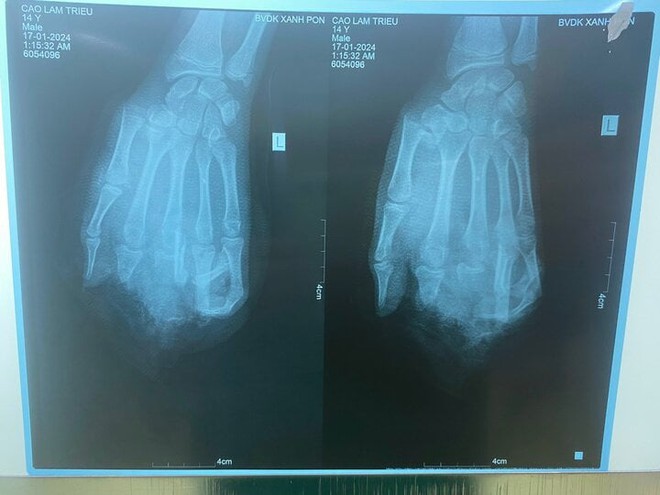

Nổ bình gas mini khi ăn lẩu, thiếu niên 15 tuổi dập nát tay - Ảnh 1.

Hình ảnh phim chụp của bệnh nhân. (Ảnh: BVCC)